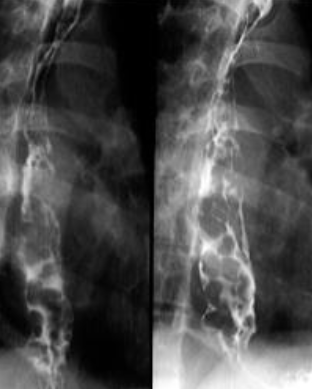

Varice esofagiene